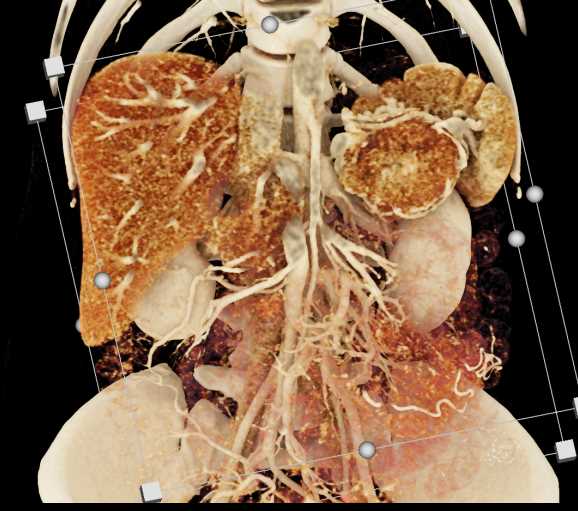

Neuroendocrine Tumor Pancreas